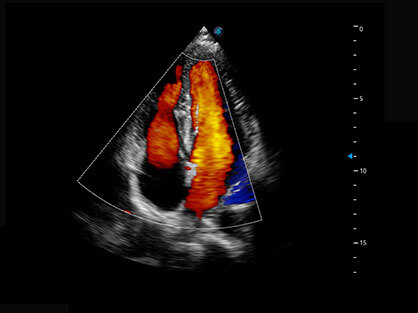

临床图